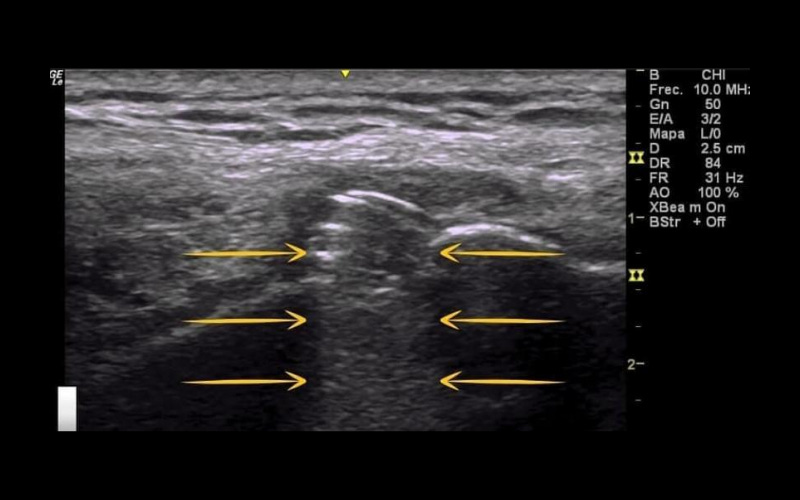

Sombra acústica posterior

"Ocurre cuando el haz del ultrasonido entra en contacto con densidad mineral ósea, generando profundo a él una sombra."

En este caso nos encontramos en un tendón rotuliano. Se observa una calcificación y cómo se genera una sombra (señalado con flechas amarillas) que corresponde a un artefacto. ¿Podríamos saber con ecografía si una calcificación es de densidad dura o blanda?

¡Por supuesto!